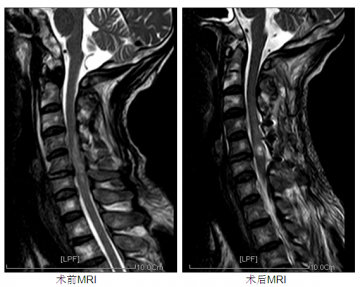

南医五院完成首例颈后路单开门减压+椎管扩大成形术

近期,南医五院脊柱外科完成首例颈后路单开门减压+椎管扩大成形术,标志着脊柱外科颈后路减压技术跃上了一个新的台阶。 6月15日凌晨1点,南医五院脊柱外科收治一位47岁男性患者,因深夜骑摩托车发生车祸,摔伤后即出现短暂昏迷,病情危重。入院时四肢无力、口鼻流血、左侧眉弓开放性伤口,深达骨面,颜面部、四肢多处擦伤出血。入...